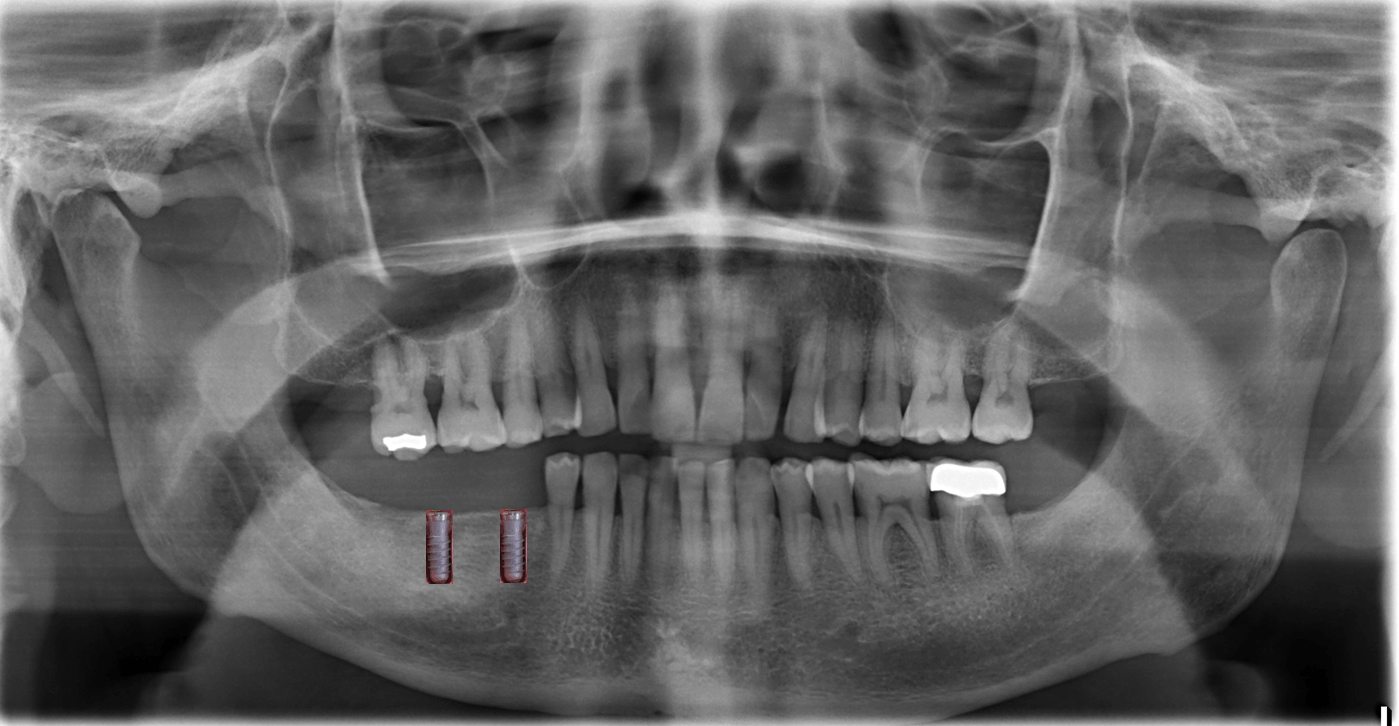

X-ray, 3D and examination

The basis of the final plan

We offer titanium and ceramic implants (two or three parts).

A 3D examination "digital volume tomography" is carried out in the DVT Center Hamburg, Lerchenfeld 14, 22081 Hamburg, Tel 040-2269-4990. They will give you the CD, which we will read here.